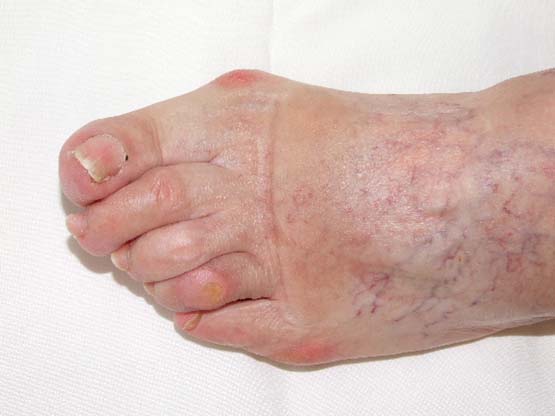

Hallus valgus. Onicomicosis.